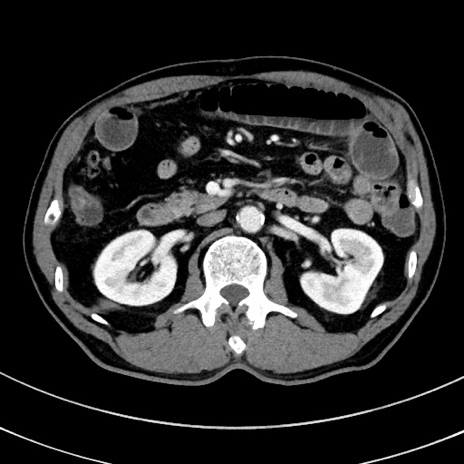

症例8(横断像)

【症例】 60歳代男性

【主訴】 黒色吐物

【現病歴】 4日前から嘔気自覚、2日前の朝食後にも嘔気あり、自分で手で嘔吐反射起こし嘔吐したところ血が混ざっていたため受診。

【既往歴】 5年前汎発性腹膜炎を伴う急性虫垂炎で手術、高血圧、前立腺肥大症、高脂血症

【身体所見】 腹部正中に手術癩痕あり 腹部平坦・軟圧痛なし膨満感あり

【データ】WBC 8400、CRP 4.54